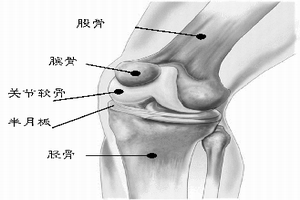

(6)腕、踝、膝及肘關節明顯膨大,下肢弓狀畸形。有時可伴有骨折,少數可有股骨頭骨骺滑脫。

骨質軟化症2.佝僂病長骨骨幹缺鈣、軟化因應力作用而彎曲,出現“O”形腿(膝內翻)、“X”形腿(膝外翻)及脛骨下部前傾,成軍刀狀畸形。嚴重佝僂病患者和嬰幼兒佝僂病可因嚴重低血鈣而出現手足搐搦,甚至可致全身驚厥、喉痙攣,發生窒息而死亡。